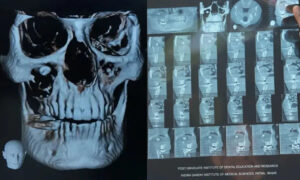

‘আমার সব কাজ আটকে গিয়েছিল। এরপর জুন মাসে আমি আইজিআইএমএসে দাঁতের চিকিৎসকের কাছে যাই। চিকিৎসক আমার সিবিসিটি স্ক্যান করান। সেখান থেকে জানতে পারি আমার চোখে দাঁত গজিয়েছে।’

সিবিসিটি সিস্টেম এমন এক ধরনের ডায়াগনস্টিক ইমাজিং টুল, যেখানে এক্স-রে রশ্মি ব্যবহার করে হাড় ও সফট টিস্যু, বিশেষ করে মাথা ও মুখ বা ‘ওরাল’ এরিয়ার হাই রেজল্যুশনের থ্রিডি ইমেজ পেতে সাহায্য করে।

রোগী রমেশ কুমারের যখন ‘কোন বিম কম্পিউটেড টোমোগ্রাফি’ বা সিবিসিটি করানো হয়, তখন দেখা যায়, তার দাঁতের গোড়া ‘ফ্লোর অব দ্য অরবিটে’ রয়েছে। ডা. প্রিয়ঙ্কর সিং ব্যাখ্যা করেন, ‘এই ক্ষেত্রে, দাঁতের গোড়া ছিল ফ্লোর অব অরবিটে। যদিও এর ক্রাউন (দাঁতের সাদা অংশ) ছিল ম্যাক্সিলারি সাইনাসে। যেহেতু এই দাঁত নিজের স্বাভাবিক স্থানে গঠিত হয়নি, তাই শরীরের কাছে এটা ফরেন বডি ছিল।’